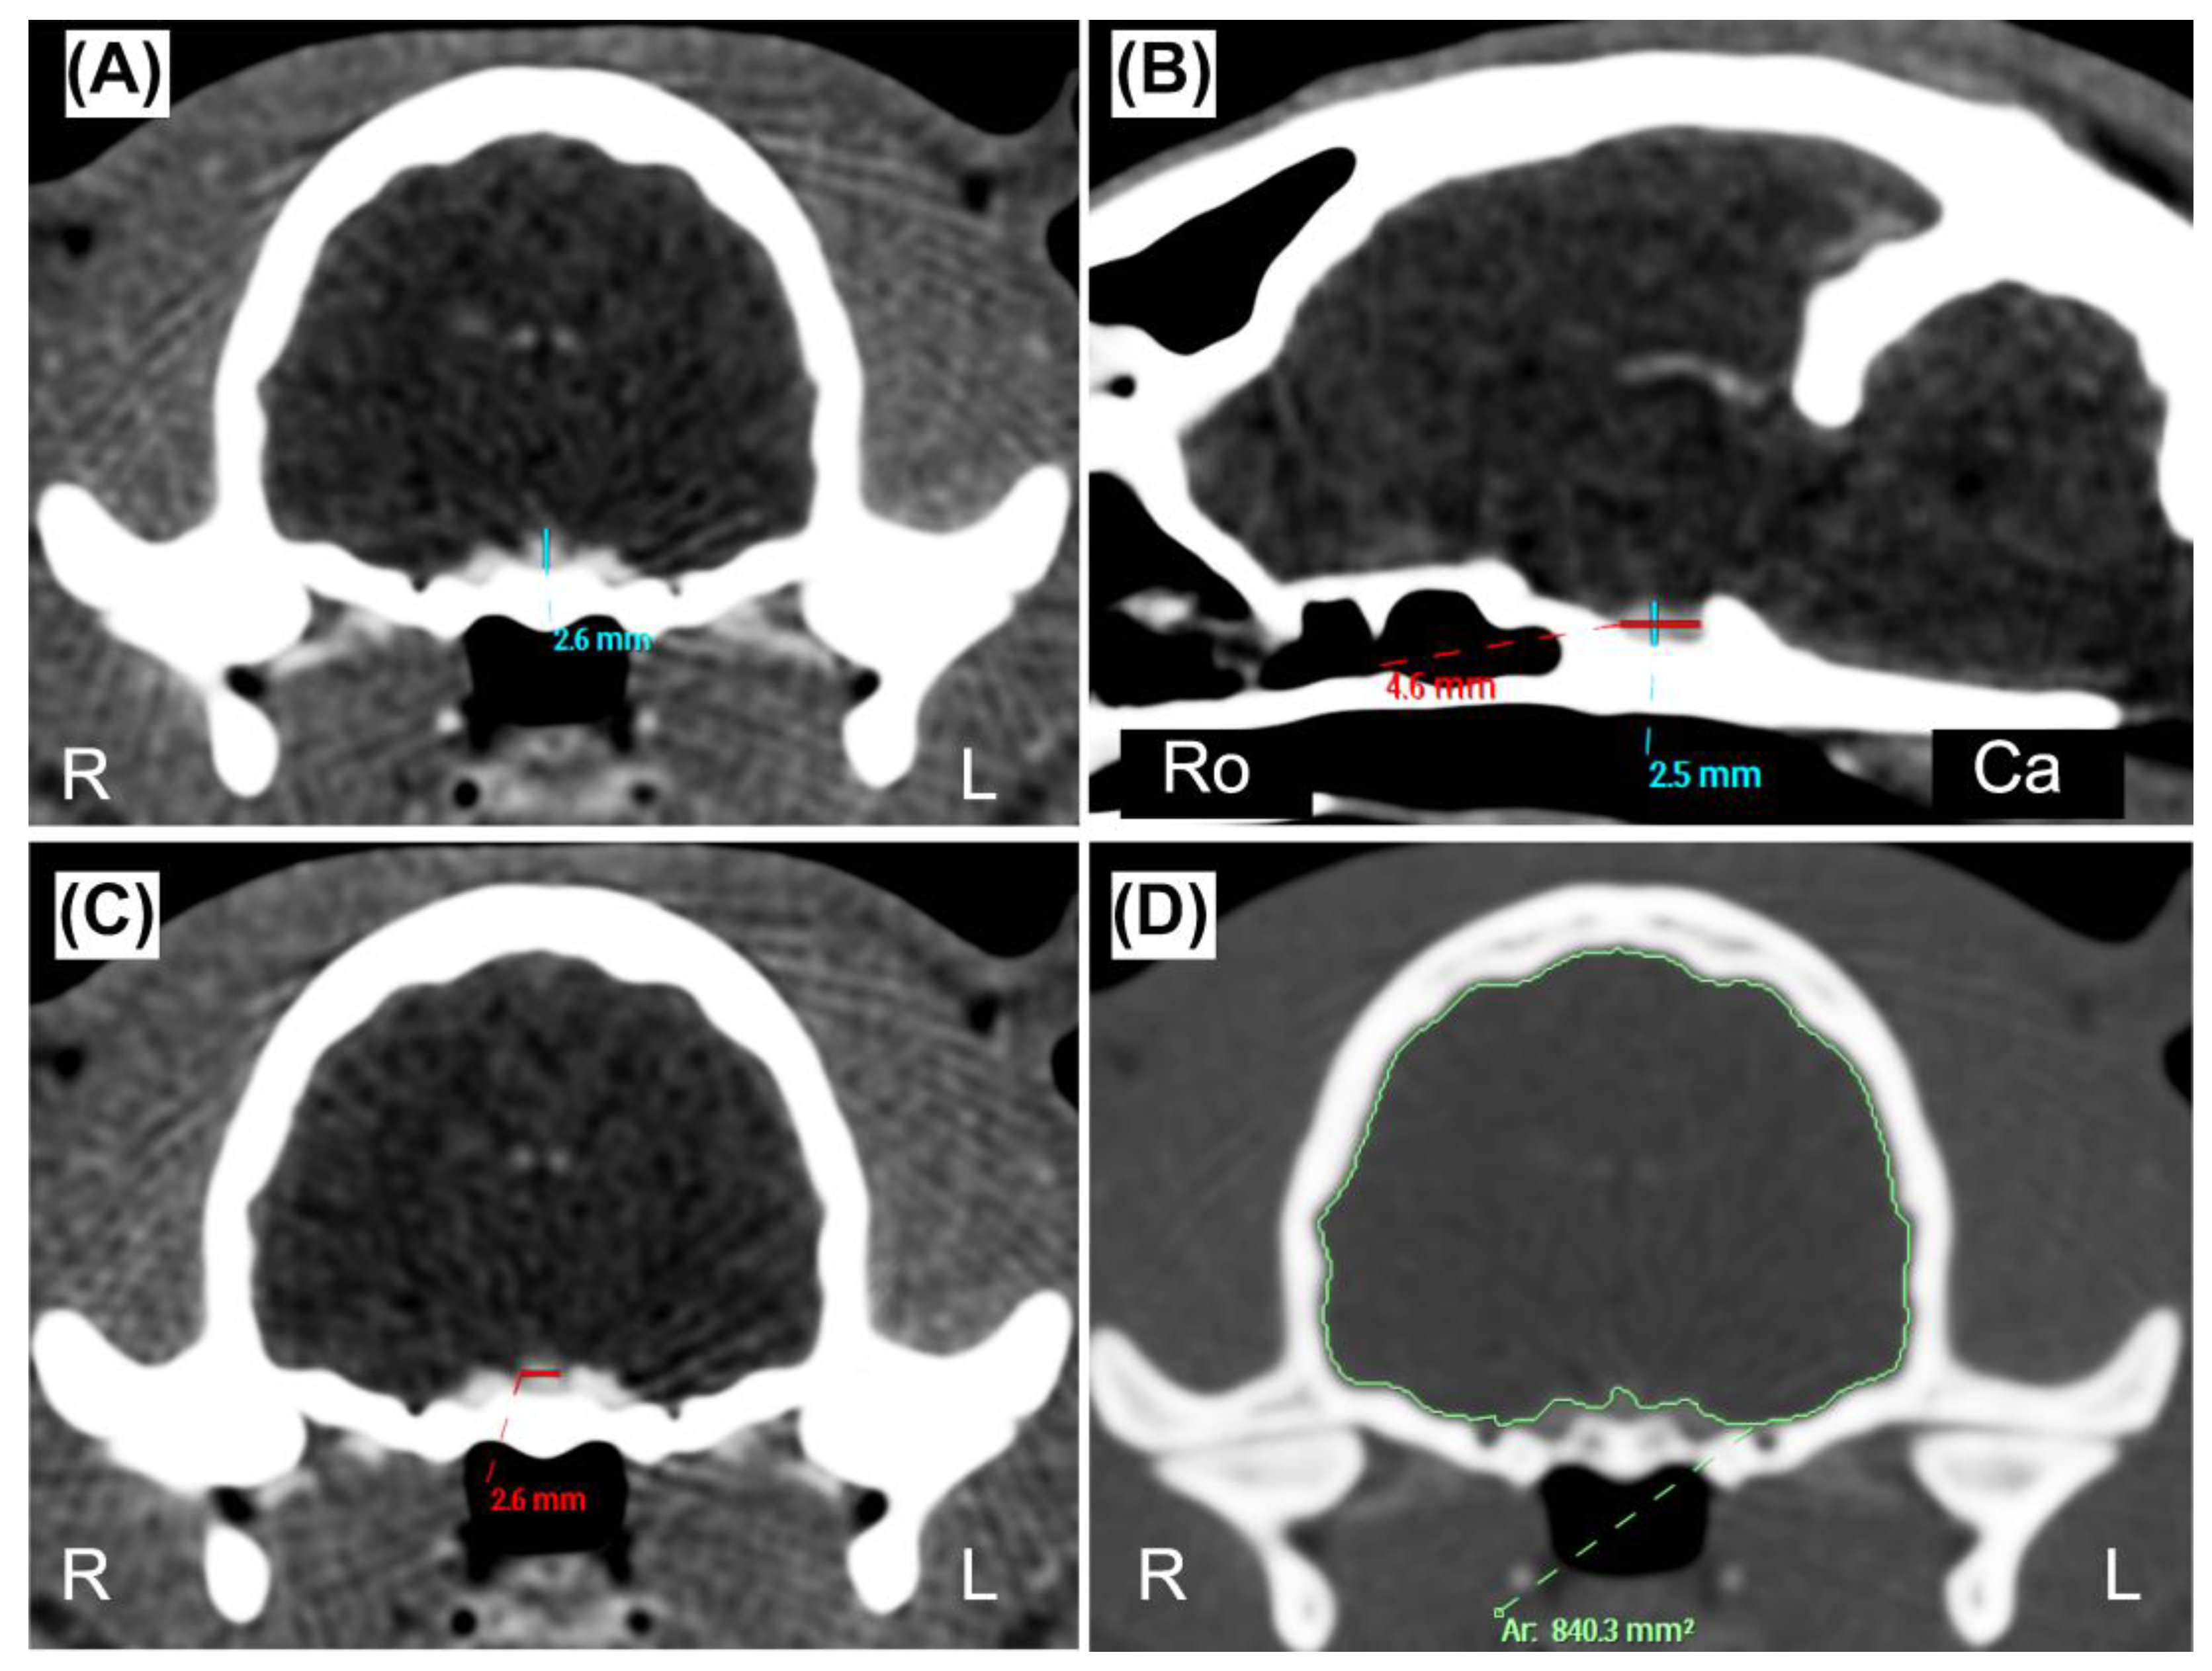

| Measurement | Mean (±SD) | Range (Min–Max) |

Lower Limit (90% CI) |

Upper Limit (90% CI |

|---|---|---|---|---|

| PHT (mm) | 2.94 (± 0.52) | 2.0 – 4.1 | 1.88 (1.68 – 2.10) |

4.01 (3.81 – 4.20) |

| PHS (mm) | 2.95 (± 0.55) | 1.9 – 4.0 | 1.84 (1.63 – 2.08) |

4.10 (3.89 – 4.27) |

| PL (mm) | 3.17 (± 0.52) | 2.0 – 4.4 | 2.13 (1.92 – 2.37) |

4.23 (4.03 – 4.42) |

| PW (mm) | 3.24 (± 0.61) | 2.1 – 4.8 | 1.92 (1.66 – 2.15) |

4.41 (4.12 – 4.71) |

| BA (mm2) | 789.02 (± 61.85) | 647.87 – 962.85 | 659.51 (634.51 – 687.61) |

910.96 (883 – 938.01) |

| P:B ratio | 0.37 (± 0.06) | 0.25 – 0.48 | 0.25 (0.23 – 0.28) |

0.49 (0.47 – 0.51) |